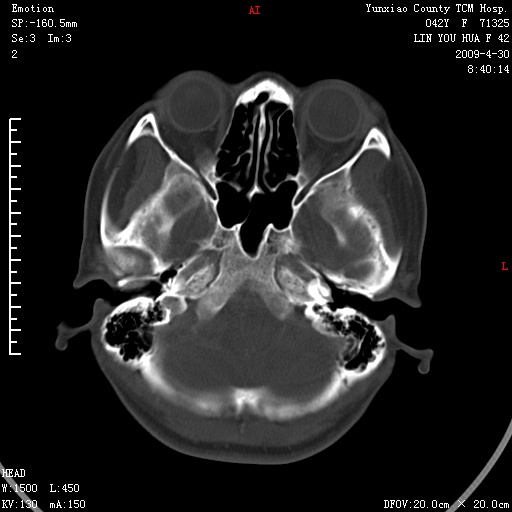

右侧桥小脑角区肿瘤,高密度囊变有显著强化,骨窗见内听道显著扩大,考虑听神经瘤可能性大

1)右侧听神经瘤。2)阻塞性脑积水。

内听道扩大,支持考虑听神经瘤可能性大。